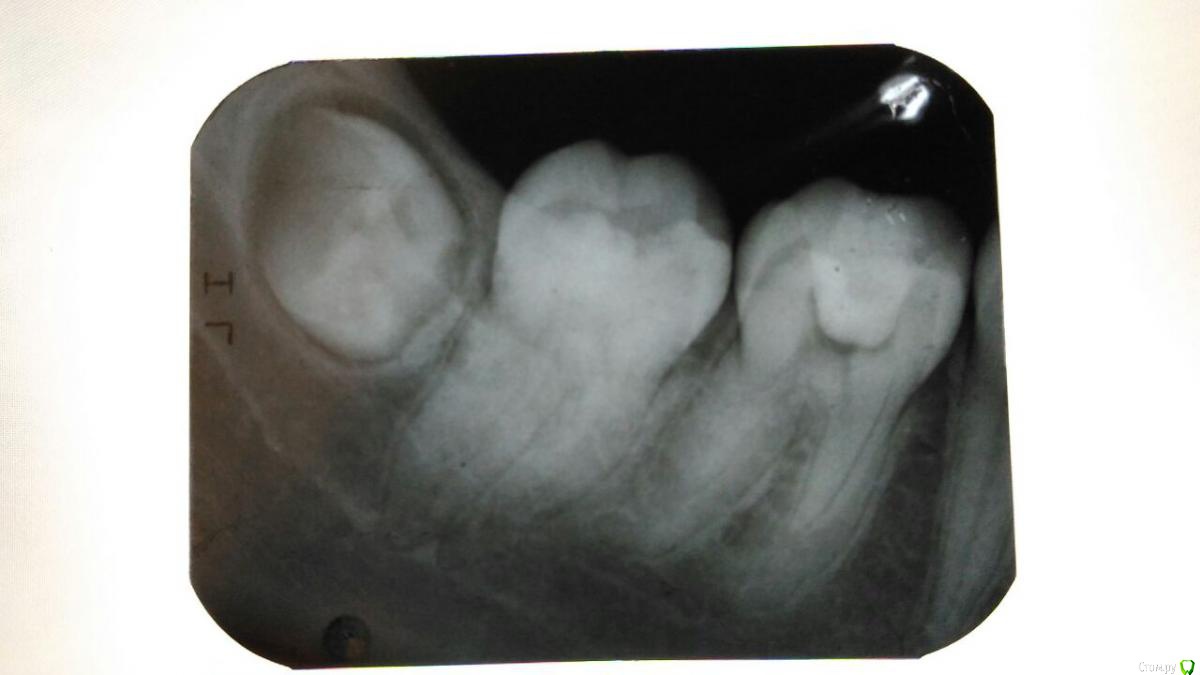

Katerina99 Опубликовано 27 декабря, 2016 Поделиться Опубликовано 27 декабря, 2016 (изменено) Здравствуйте, мне врач лечил зуб и выписал направление на рентген. Что можете сказать о состоянии шестерки и соседних зубов? http://radikal.ru/fp/86ubig91pn2bh Изменено 27 декабря, 2016 пользователем Katerina99 Ссылка на комментарий

Katerina99 Опубликовано 27 декабря, 2016 Автор Поделиться Опубликовано 27 декабря, 2016 Вас сейчас что-то беспокоит? По какому поводу направили на снимок? Небольшой дискомфорт есть и привкус лекарств иногда. Завтра я с этим снимком иду на итоговое лечение. В первый раз мне врач ставил временную пломбу, через некоторое время убрал ее, прочистил каналы, чем-то обработал и заделал новой пломбой с условием, что я сделаю рентген и приду на прием. Ссылка на комментарий

Katerina99 Опубликовано 27 декабря, 2016 Автор Поделиться Опубликовано 27 декабря, 2016 А зуб в цвете не изменен? Ну как сказать? Сброку было темное пятно и, как я поняла, на жевательной поверхности вторичный кариес. Врач убил нерв, прочистил каналы, сделал пломбу и сказал, чтобы я к нему со снимком пришла. Ссылка на комментарий

St. Опубликовано 27 декабря, 2016 Поделиться Опубликовано 27 декабря, 2016 По снимку видно пломбу в полости зуба и корневые каналы без контрастного материала. Ссылка на комментарий

St. Опубликовано 28 декабря, 2016 Поделиться Опубликовано 28 декабря, 2016 Что за контрастный материал?Поясню. Сейчас в каналах корня где раньше был нерв или ничего нет или материал не видимый на снимке,т.е.неконтрастный.Когда каналы пломбируйте постоянно их в подавляющем большинстве случаев закрывают рентген контрастными материалами. За счет этого можно увидеть белые полоски на снимке там где раньше был "нерв" Ссылка на комментарий